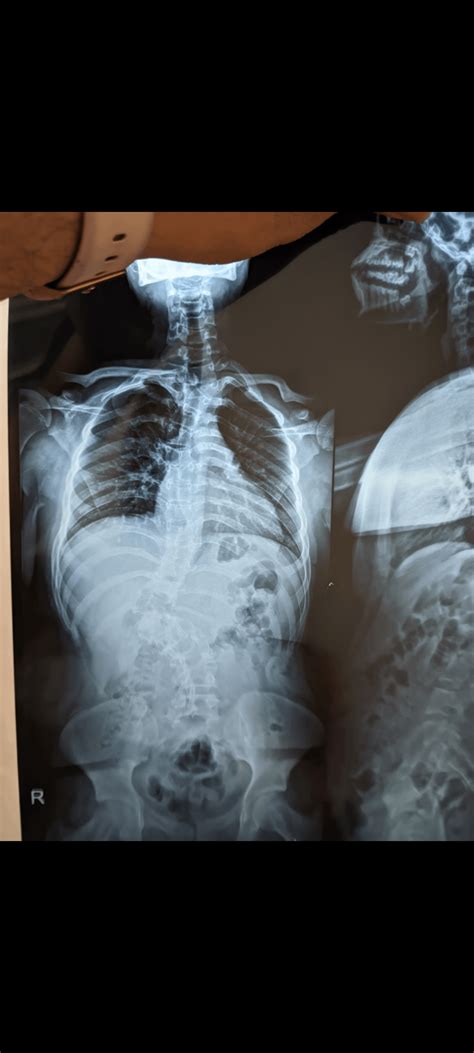

The Scoliosis Cobb Angle is a radiographic measurement used to quantify the magnitude of spinal deformity in patients with scoliosis. It was first introduced by Dr. John Robert Cobb in 1948 and has since become the definitive tool for orthopedic specialists worldwide. By identifying the most tilted vertebrae at the top and bottom of a spinal curve, clinicians can draw specific lines on an X-ray to calculate the severity of the curve.

When you look at your X-ray, the spine might appear to have a lateral shift. The Cobb angle turns that visual observation into a data point. The measurement helps medical professionals distinguish between mild postural shifts and significant structural scoliosis that may require long-term management.

• Identify the End Vertebrae: The physician selects the vertebrae at the top and bottom of the curve that are tilted the most toward the concavity of the curve.

• Draw Parallel Lines: A line is drawn along the superior endplate of the top vertebra and another along the inferior endplate of the bottom vertebra.

• Calculate the Intersection: Perpendicular lines are drawn from these two lines until they intersect. The angle formed at the intersection of these lines is the Scoliosis Cobb Angle.